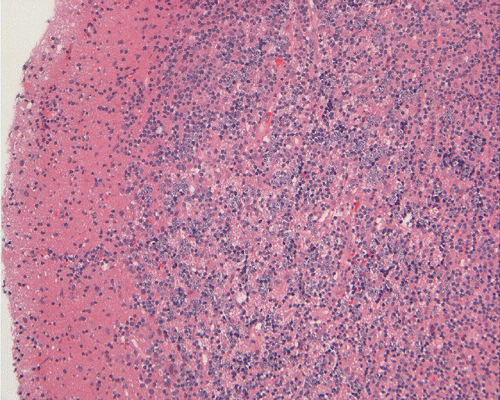

Microscopically, the morphology is similar to the corresponding type of lymphoma that occurs in other parts of the body. The neoplastic cells demonstrate a classic perivascular infiltration that dissects the perivascular reticulin network. Geographic necrosis may be seen when tumors become confluent, with perivascular islands of viable tumor cells surrounded by large regions of coagulative necrosis. As most of the PCNSL are of diffuse large B-cell type, the neoplastic cells are typically highly pleomorphic and large. Low-grade lymphomas are relatively uncommon.

Their immunohistochemical profiles are similar to lymphomas that occur outside the central nervous system. Intraoperative recognition of an atypical lymphoproiferative lesion is important as fresh tissue can be sent for flow cytometry which is often an important adjunct for correct diagnosis.